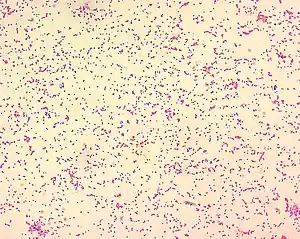

| Brucella spp. are seen mostly as single cells and appearing like “fine sand”. | |

Processed using the Gram-stain method, photomicrograph revealed the presence of numerous Gram-negative, coccobacillus, Brucella suis bacteria. -